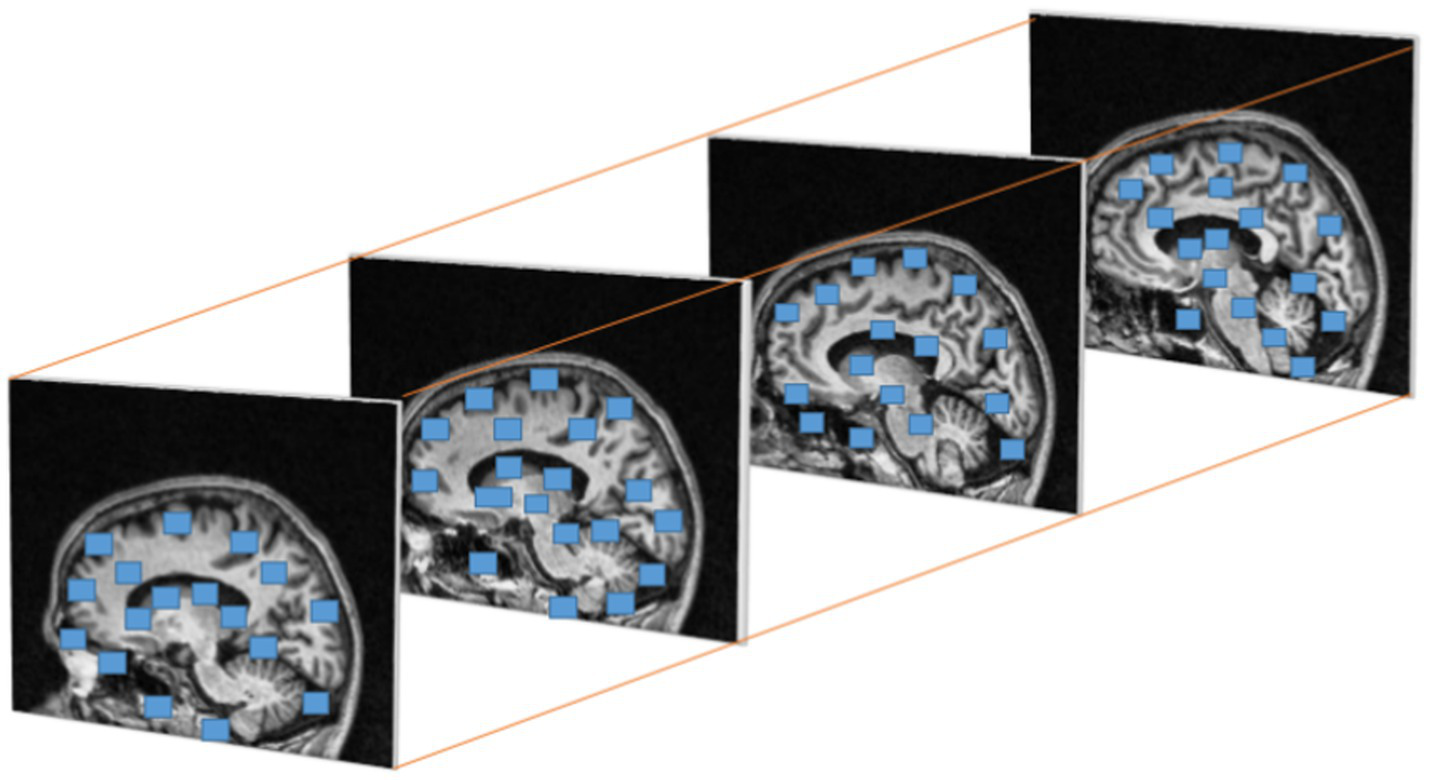

Where is , is and the are the Eigen values of M. When a window with value R exceeds the threshold point is defined as interest points with corner. Figure 6 represents the discovered interest points within the MRI slices of the dataset. Points of interest in the local maximum response function are spatiotemporal points that have been highlighted.

Figure 6

Cuboids from Harris corner interest points in brain MRI.